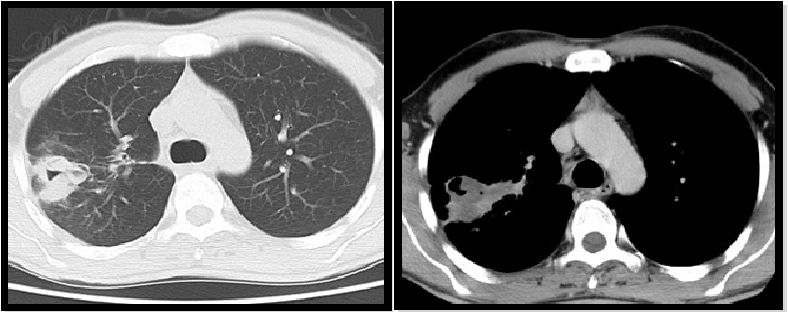

图3:轴向CT显示55岁女性的曲霉病患者发现空气新月形上叶与固结区域相关,周围有磨玻璃样改变。

图4:轴位CT显示右下叶的团块,中央区域为空洞,考虑诊断为曲霉菌,术后诊断为肺癌。